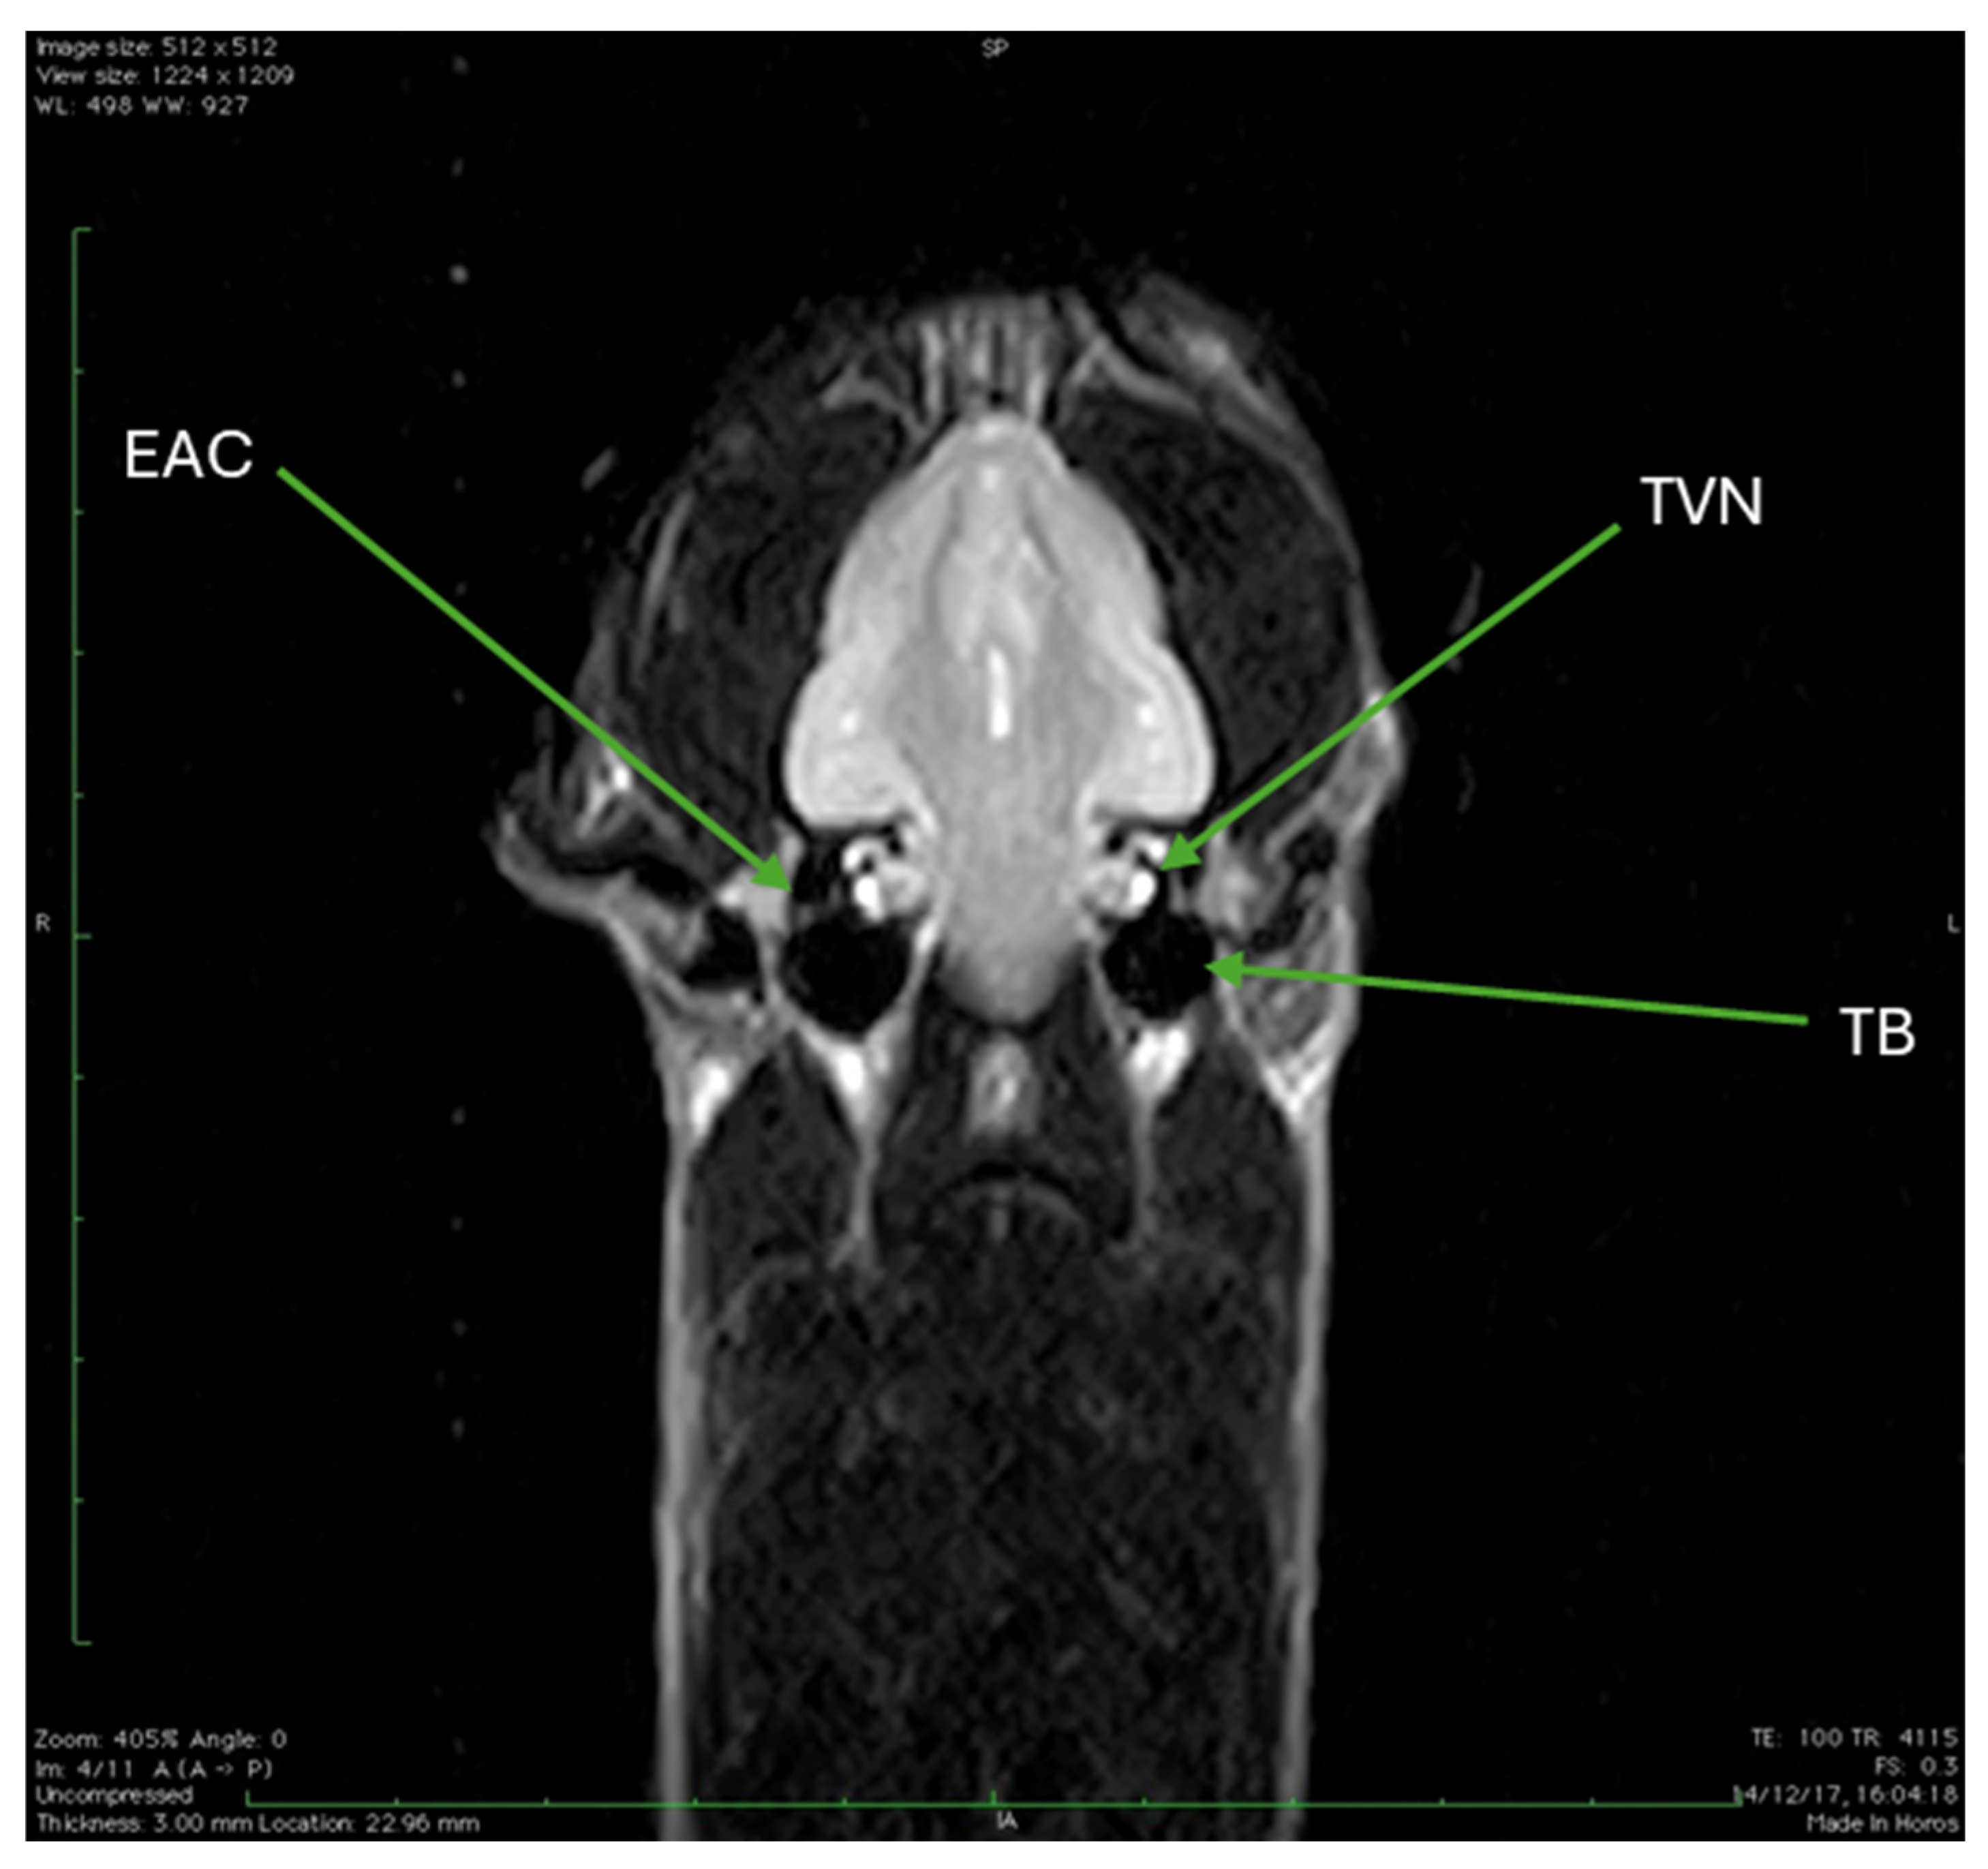

| EAC | External auditory canal |

| TVN | Trochlear vestibular nerve |

| TB | Tympanic bulla |